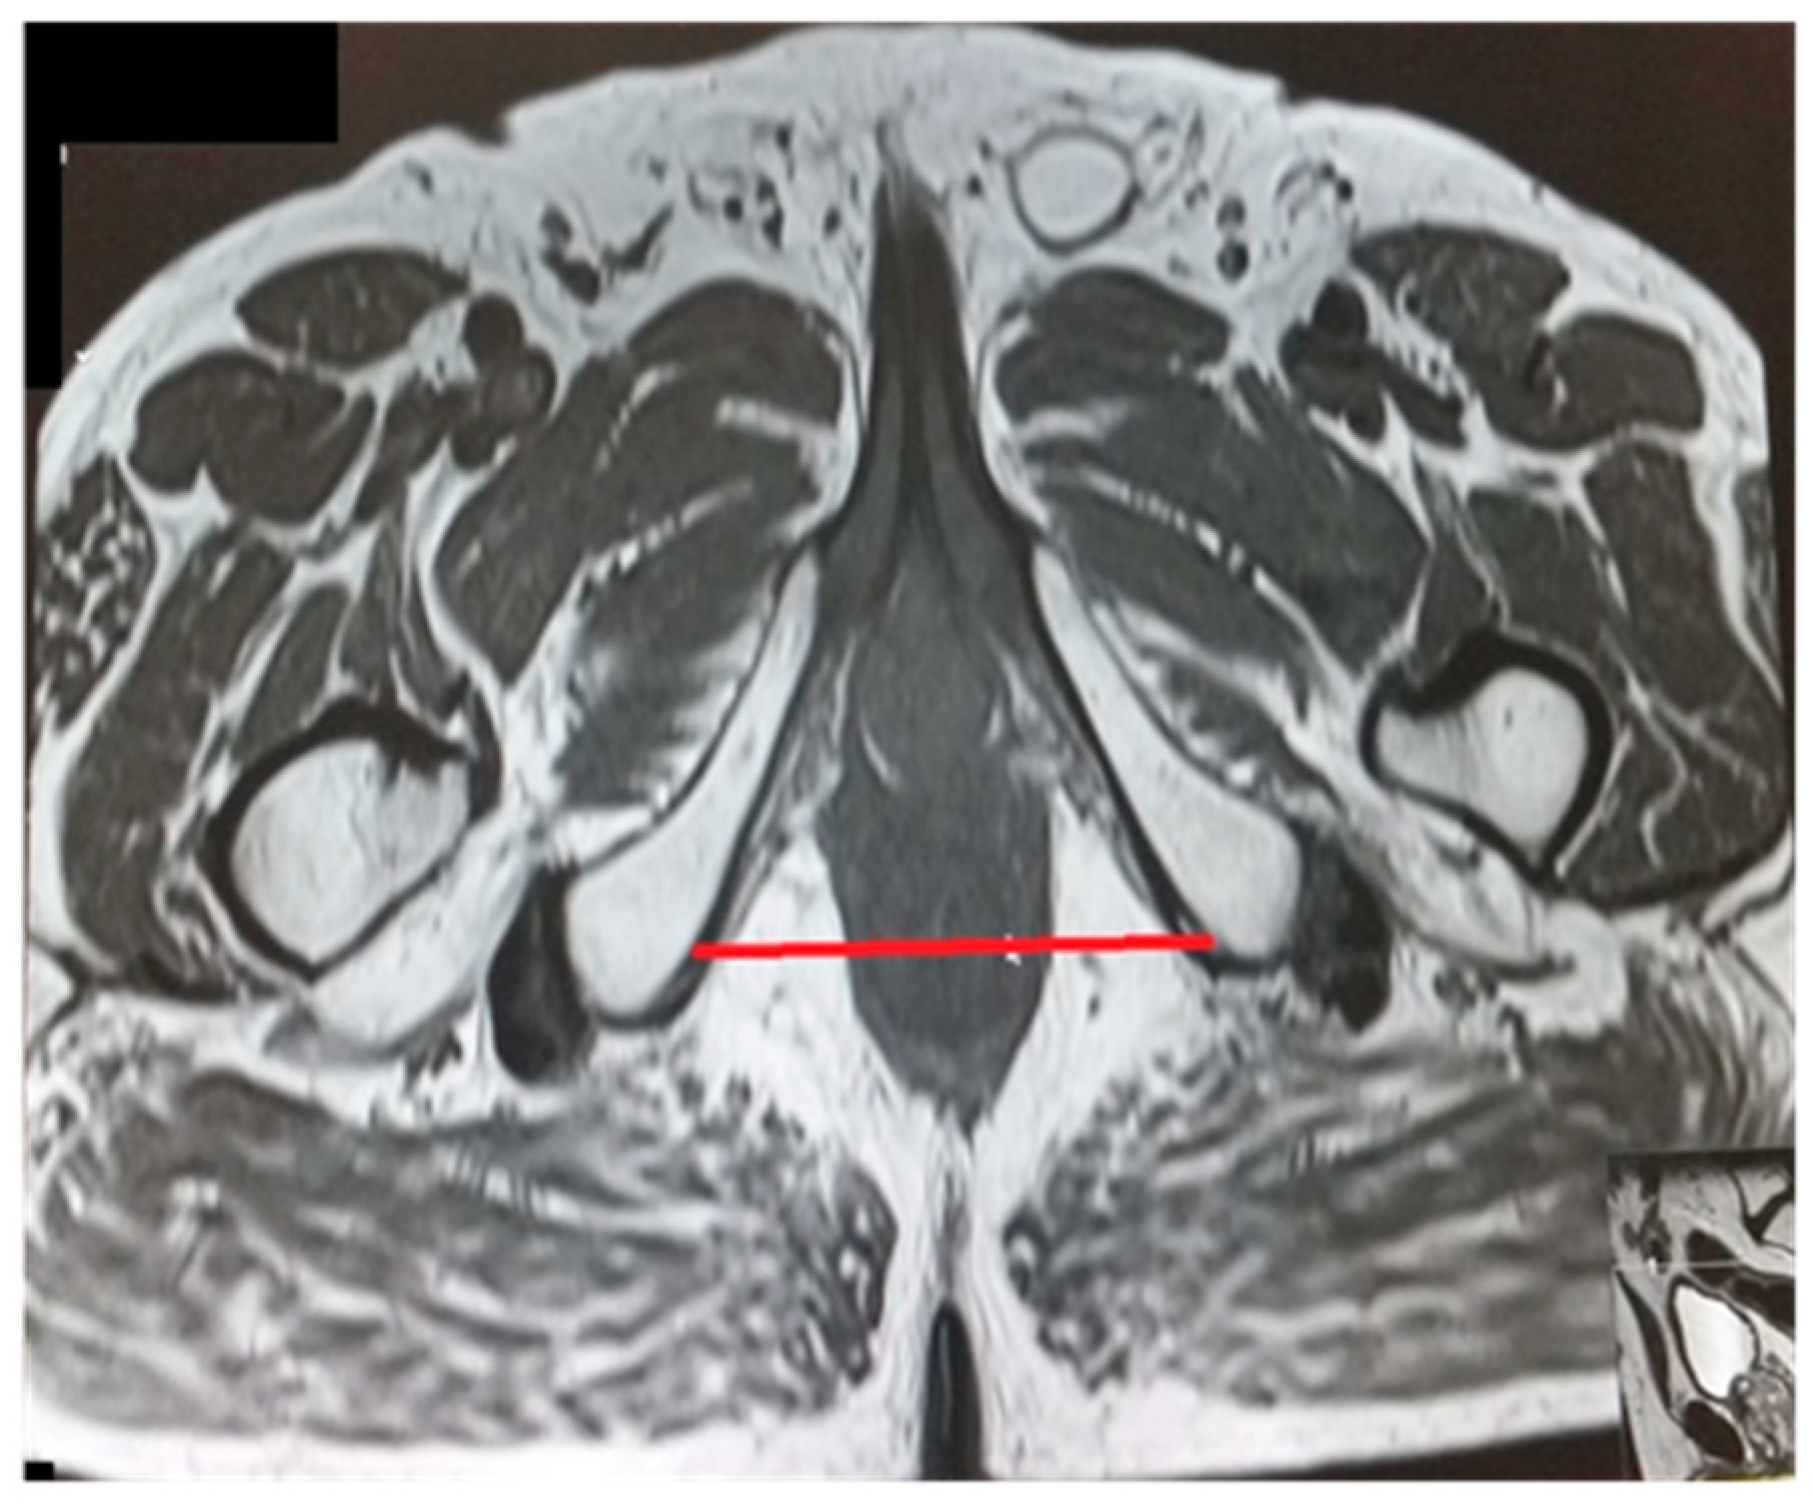

The pelvic measurements on MRI (Figure 2, Figure 3, Figure 4, Figure 5, Figure 6 and Figure 7) were carried out by the author, and to maintain the reproducibility of the results, measurements were taken, whenever possible, at the same anatomical levels.

Figure 3.

Transverse diameter.